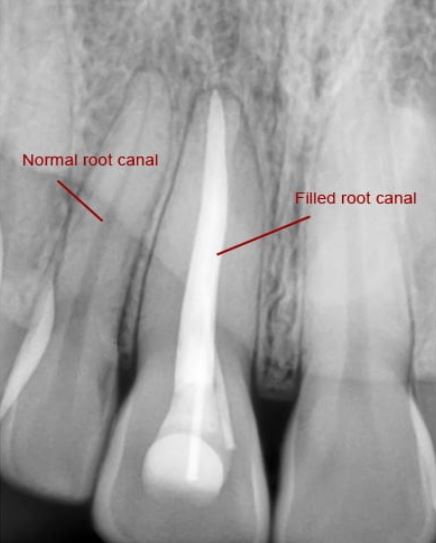

X-ray:

X-ray is indispensable for a root canal procedure and is the first step as well. In order to determine the cause of your pain and the extent of decay, one of the first things your dentist does is take an x-ray of the affected tooth. After an x-ray is taken, in most cases, the next step is to inject a local anaesthetic to ensure you have a painless procedure. In some cases, however, since the patient is asymptomatic or the tooth is completely dead and painless, local anaesthesia may be omitted.

Sealing the canals with inert material and a sealant: In ideal cases, the canals can be sealed with the inert rubber-based material in the same sitting itself. Such a RCT treatment is called as single-sitting root canal. However, in practise, most cases require a gap of 3-5 days before the canals can be permanently sealed. In the interim, the dentist places a calcium-based medication to allow the inflamed tissues to heal. Once the canals are ready to be sealed, rubber-based cones are placed into the canals and sealed. These cones are inert in nature and do not dissolve in saliva or blood and thereby, prevent re-infection of the tooth.